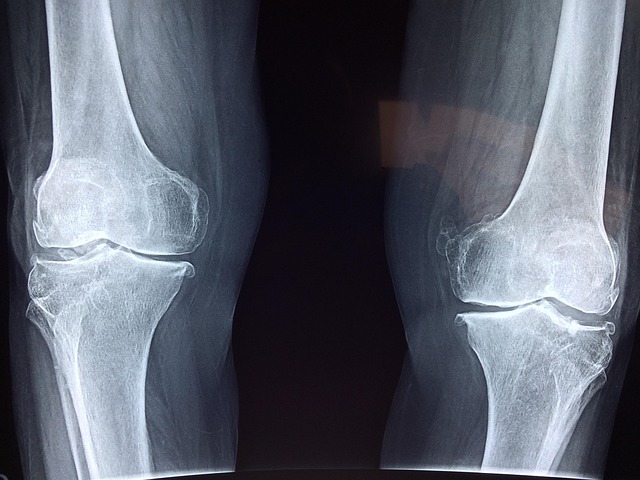

콘드로이친은 관절 연골의 주요 구성 성분으로, 골관절염 증상 완화에 도움을 주는 건강 보조제입니다. 임상 연구를 기반으로 한 정확한 콘드로이친 복용법을 알아보겠습니다.

일부 연구에서는 최대 2–3년까지 장기 콘드로이친 복용기간을 유지했으며, 관절 간격 협착(JSN) 진행을 늦추는 구조적 효과가 확인되었습니다:

- 2년 복용 시 최소 관절 간격 너비 감소가 위약군 0.30mm 대비 콘드로이친군 0.12mm로 60% 감소했습니다